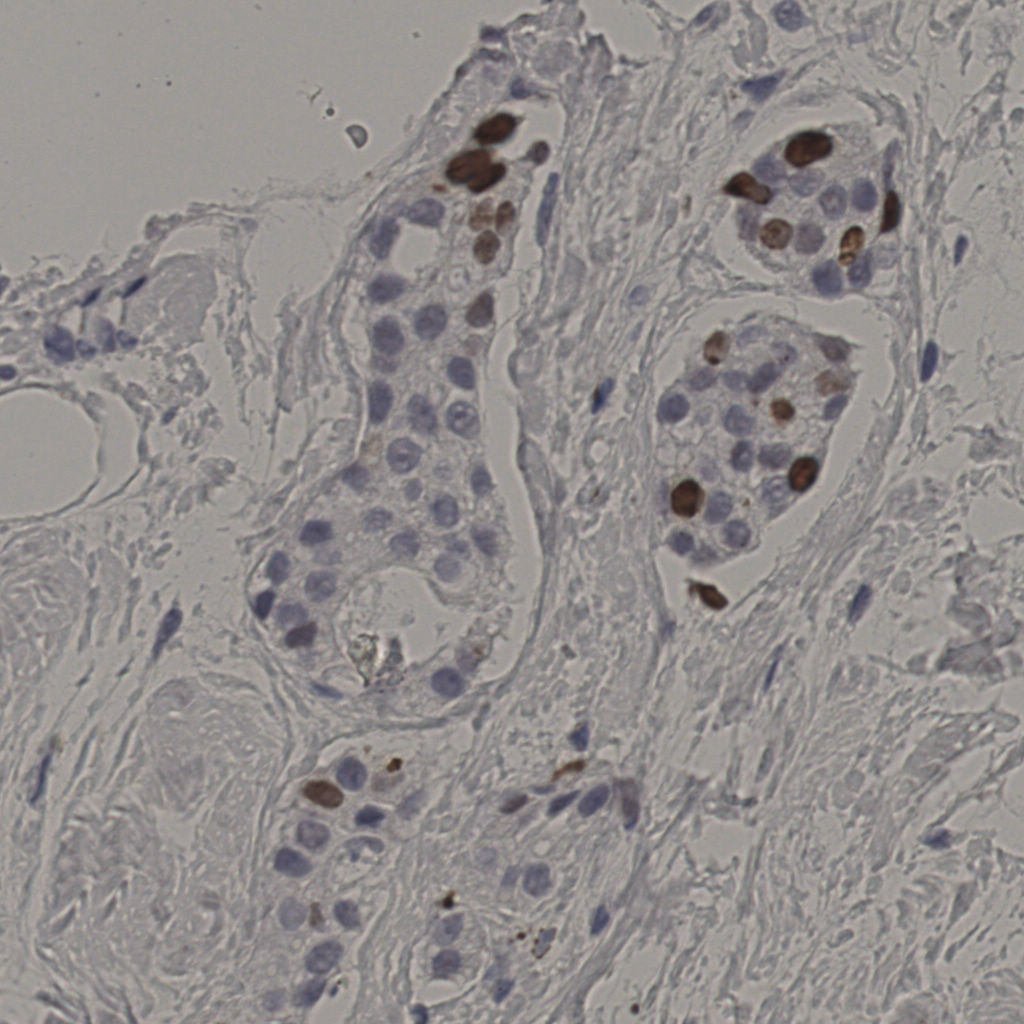

标记后

标记前

5.31%

Ki67 指数

阴 19502

阳 1093

切片统计

总切片

2970

有效

554

有效率